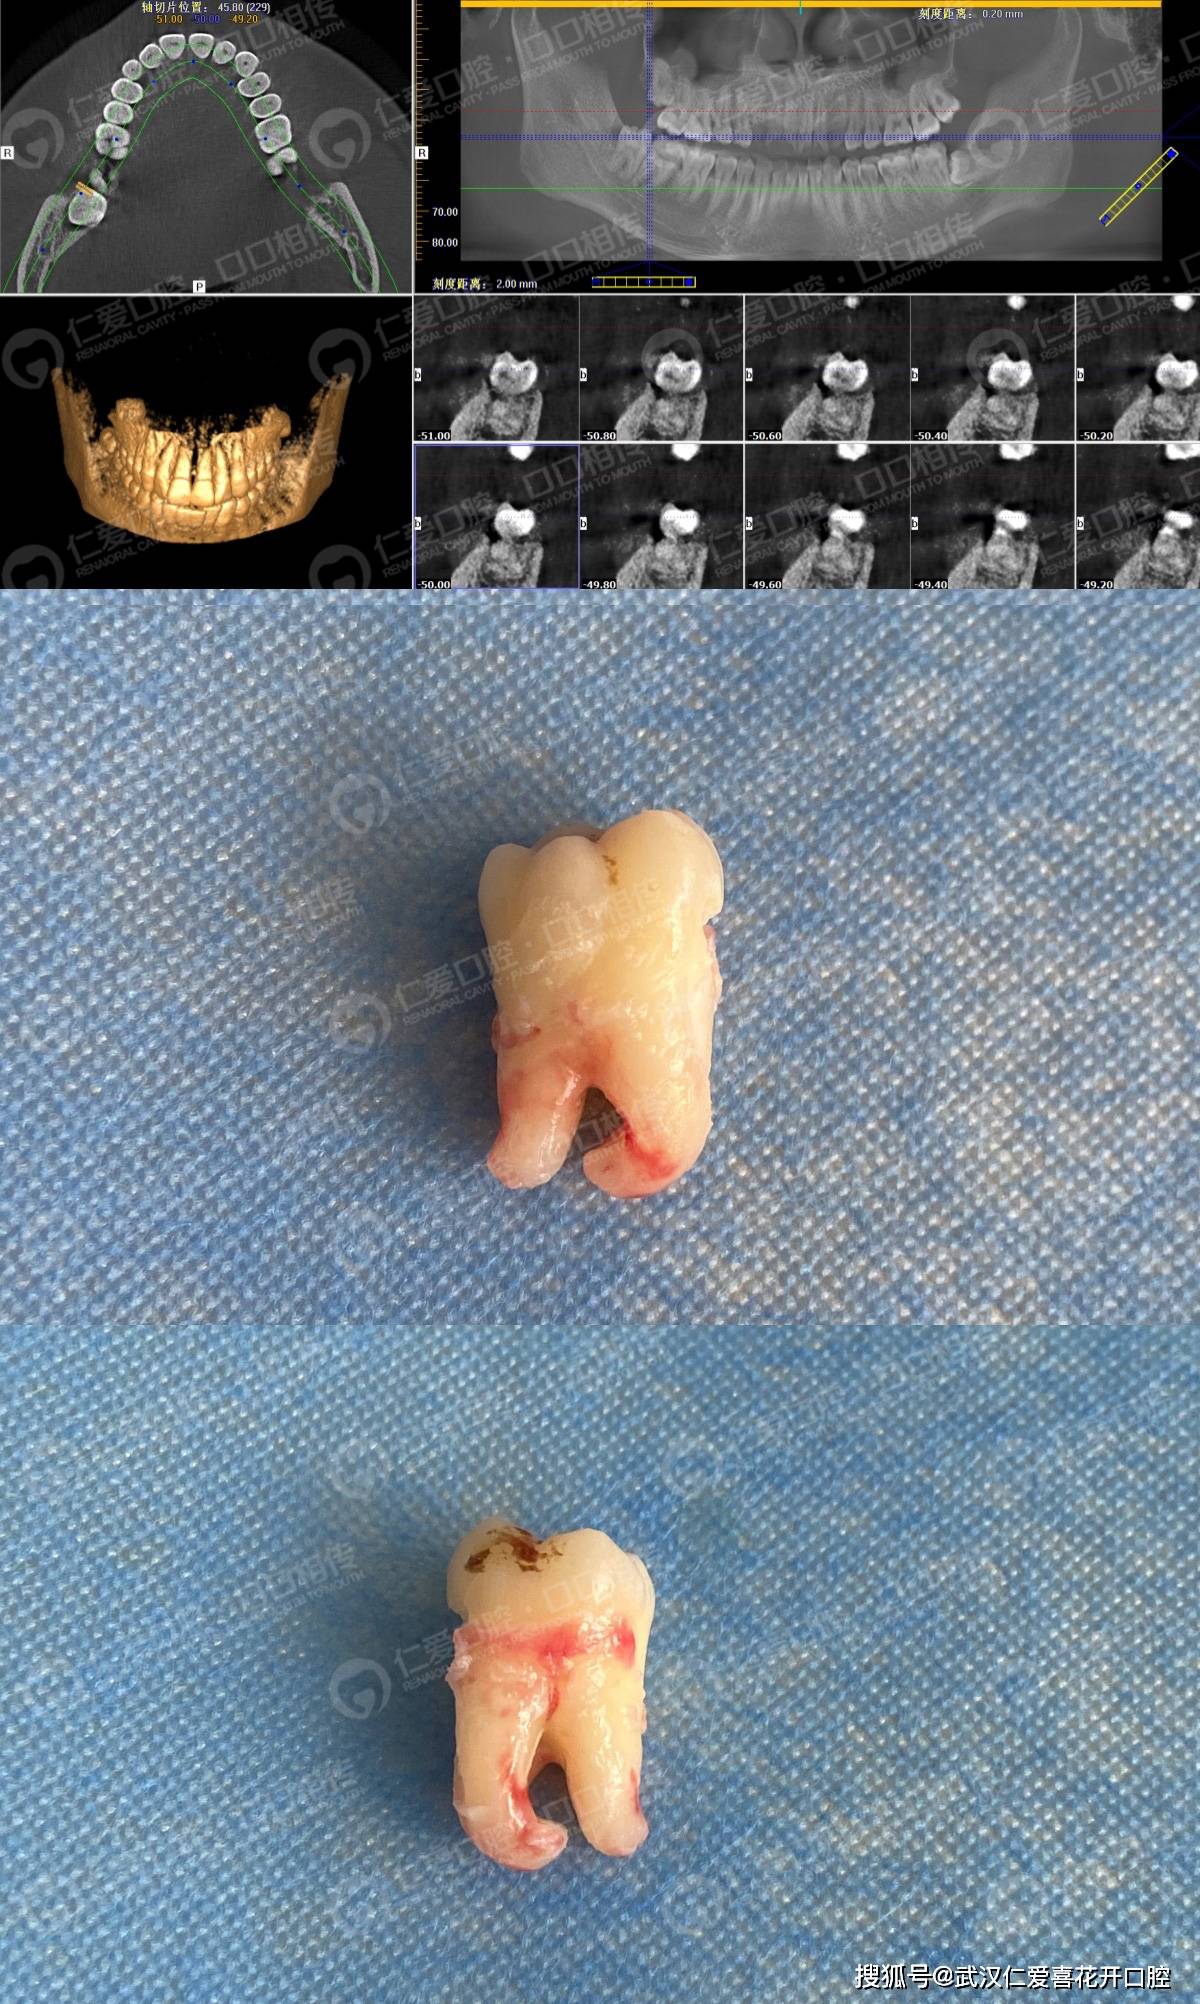

真实案例超声骨刀微创拔除下颌阻生智齿